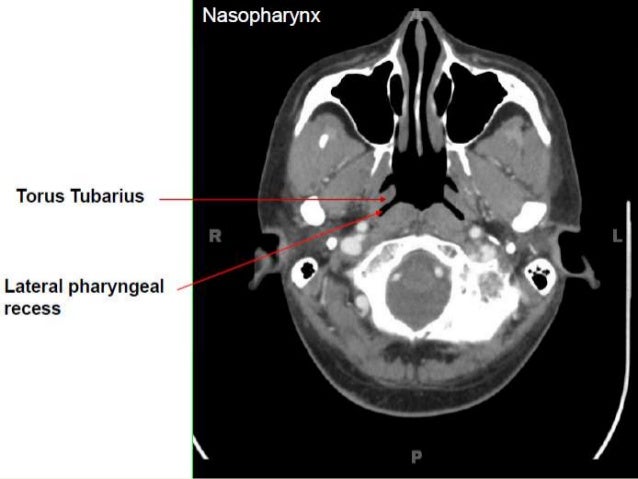

Learn vocabulary, terms and more with flashcards, games and other study tools. The torus tubarius is very close to the tubal tonsil which is sometimes also called the tonsil of (the) torus tubarius. A protrusion on the lateral wall of the nasopharynx marking the pharyngeal end of the cartilaginous part of the eustachian tube.